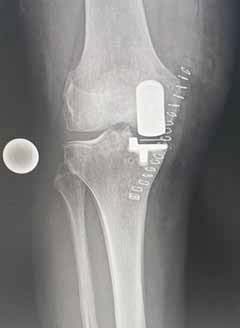

- Umstellungsosteomie

Dabei werden fehlerhafter Beinachsen operativ korrigiert.

Hohe valgisierende tibiale Umstellungsosteotomie

Unikonyläre Schlittenprothese